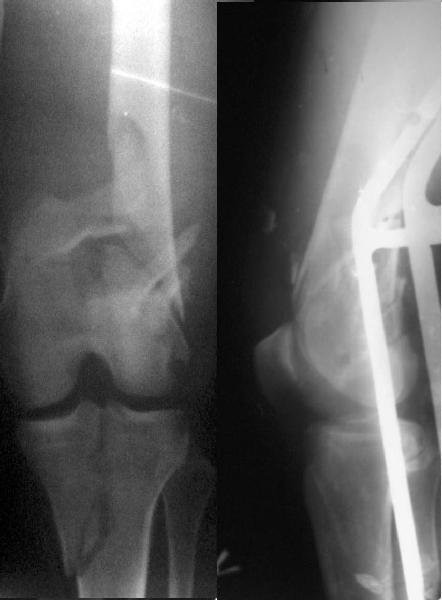

Re: Open supracondylar femur fx

And why LISS is superior here than nail?

Look what we would have done.